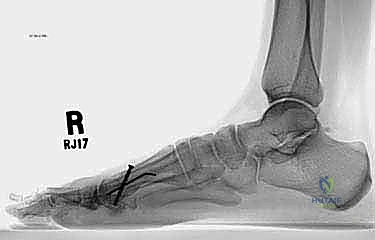

* الأشعة السينية العادية (X-rays) أثناء الوقوف: هذا هو الفحص الأهم. يتم أخذ صور للقدمين أثناء تحمل الوزن لقياس زوايا العظام بدقة، وتحديد مقدار النقص في طول مشط القدم الأول مقارنة بالثاني (يجب أن يكونا متقاربين في الطول ضمن نسب محددة).

* التصوير المقطعي المحوسب (CT Scan): يُطلب في الحالات المعقدة لتقييم جودة العظم المتبقي والتخطيط الدقيق للقص الجراحي ثلاثي الأبعاد.